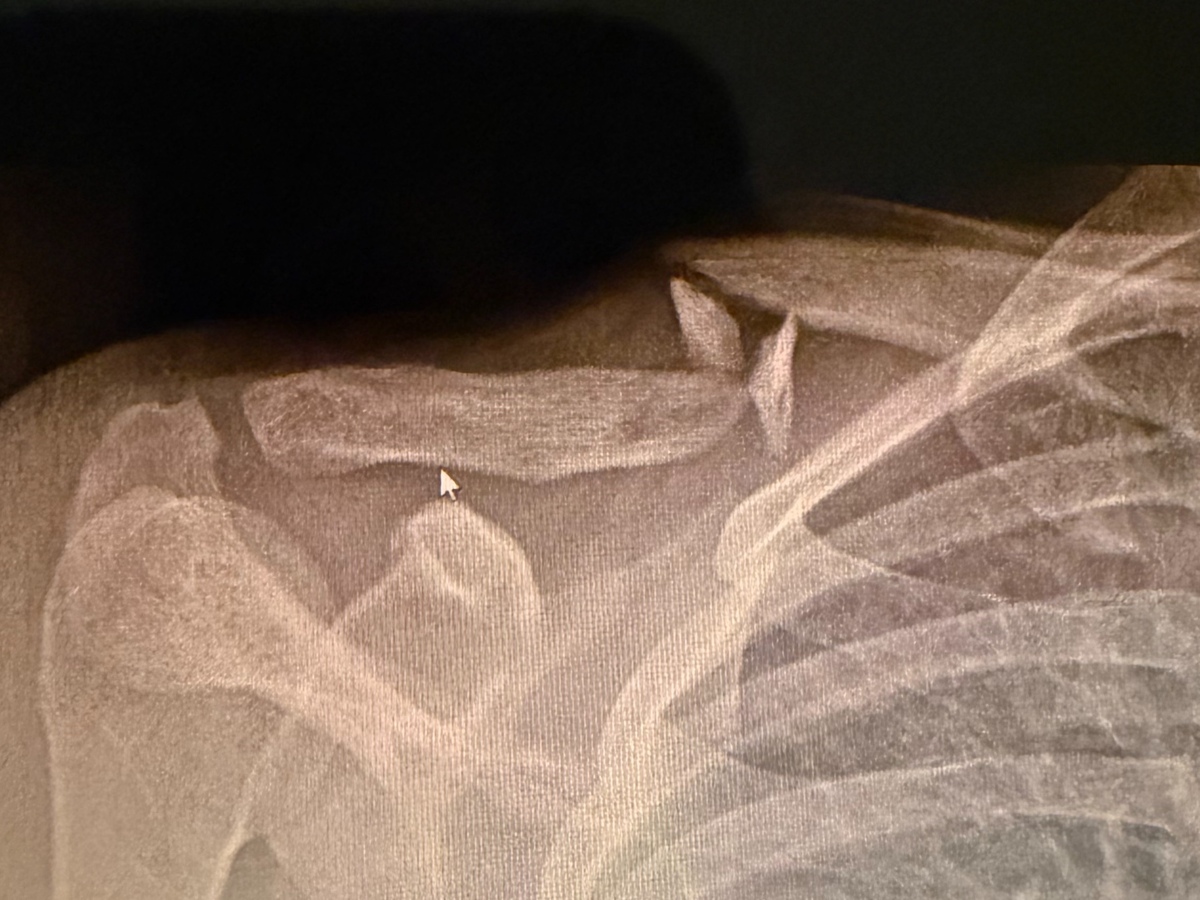

We are reaching out to community to raise funds for our deeply loved friend and community member Cewa (@anommalouss). On Jan 11, Cewa got into a bike accident that left their collarbone broken. Cewa is a private care assistant and works for disabled people, physically lifting and transferring folks multiple times a day. They also work under the table and do not qualify for any governmental assistance because of that. They do not receive sick pay as well. They are about to undergo surgery and cannot work for 2 months, potentially more, due to the nature of this injury and their line of work.